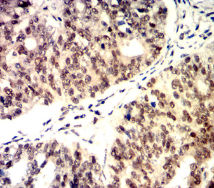

CDK4 Mouse Monoclonal antibody[4A11E]

IHC    1/200 - 1/1000